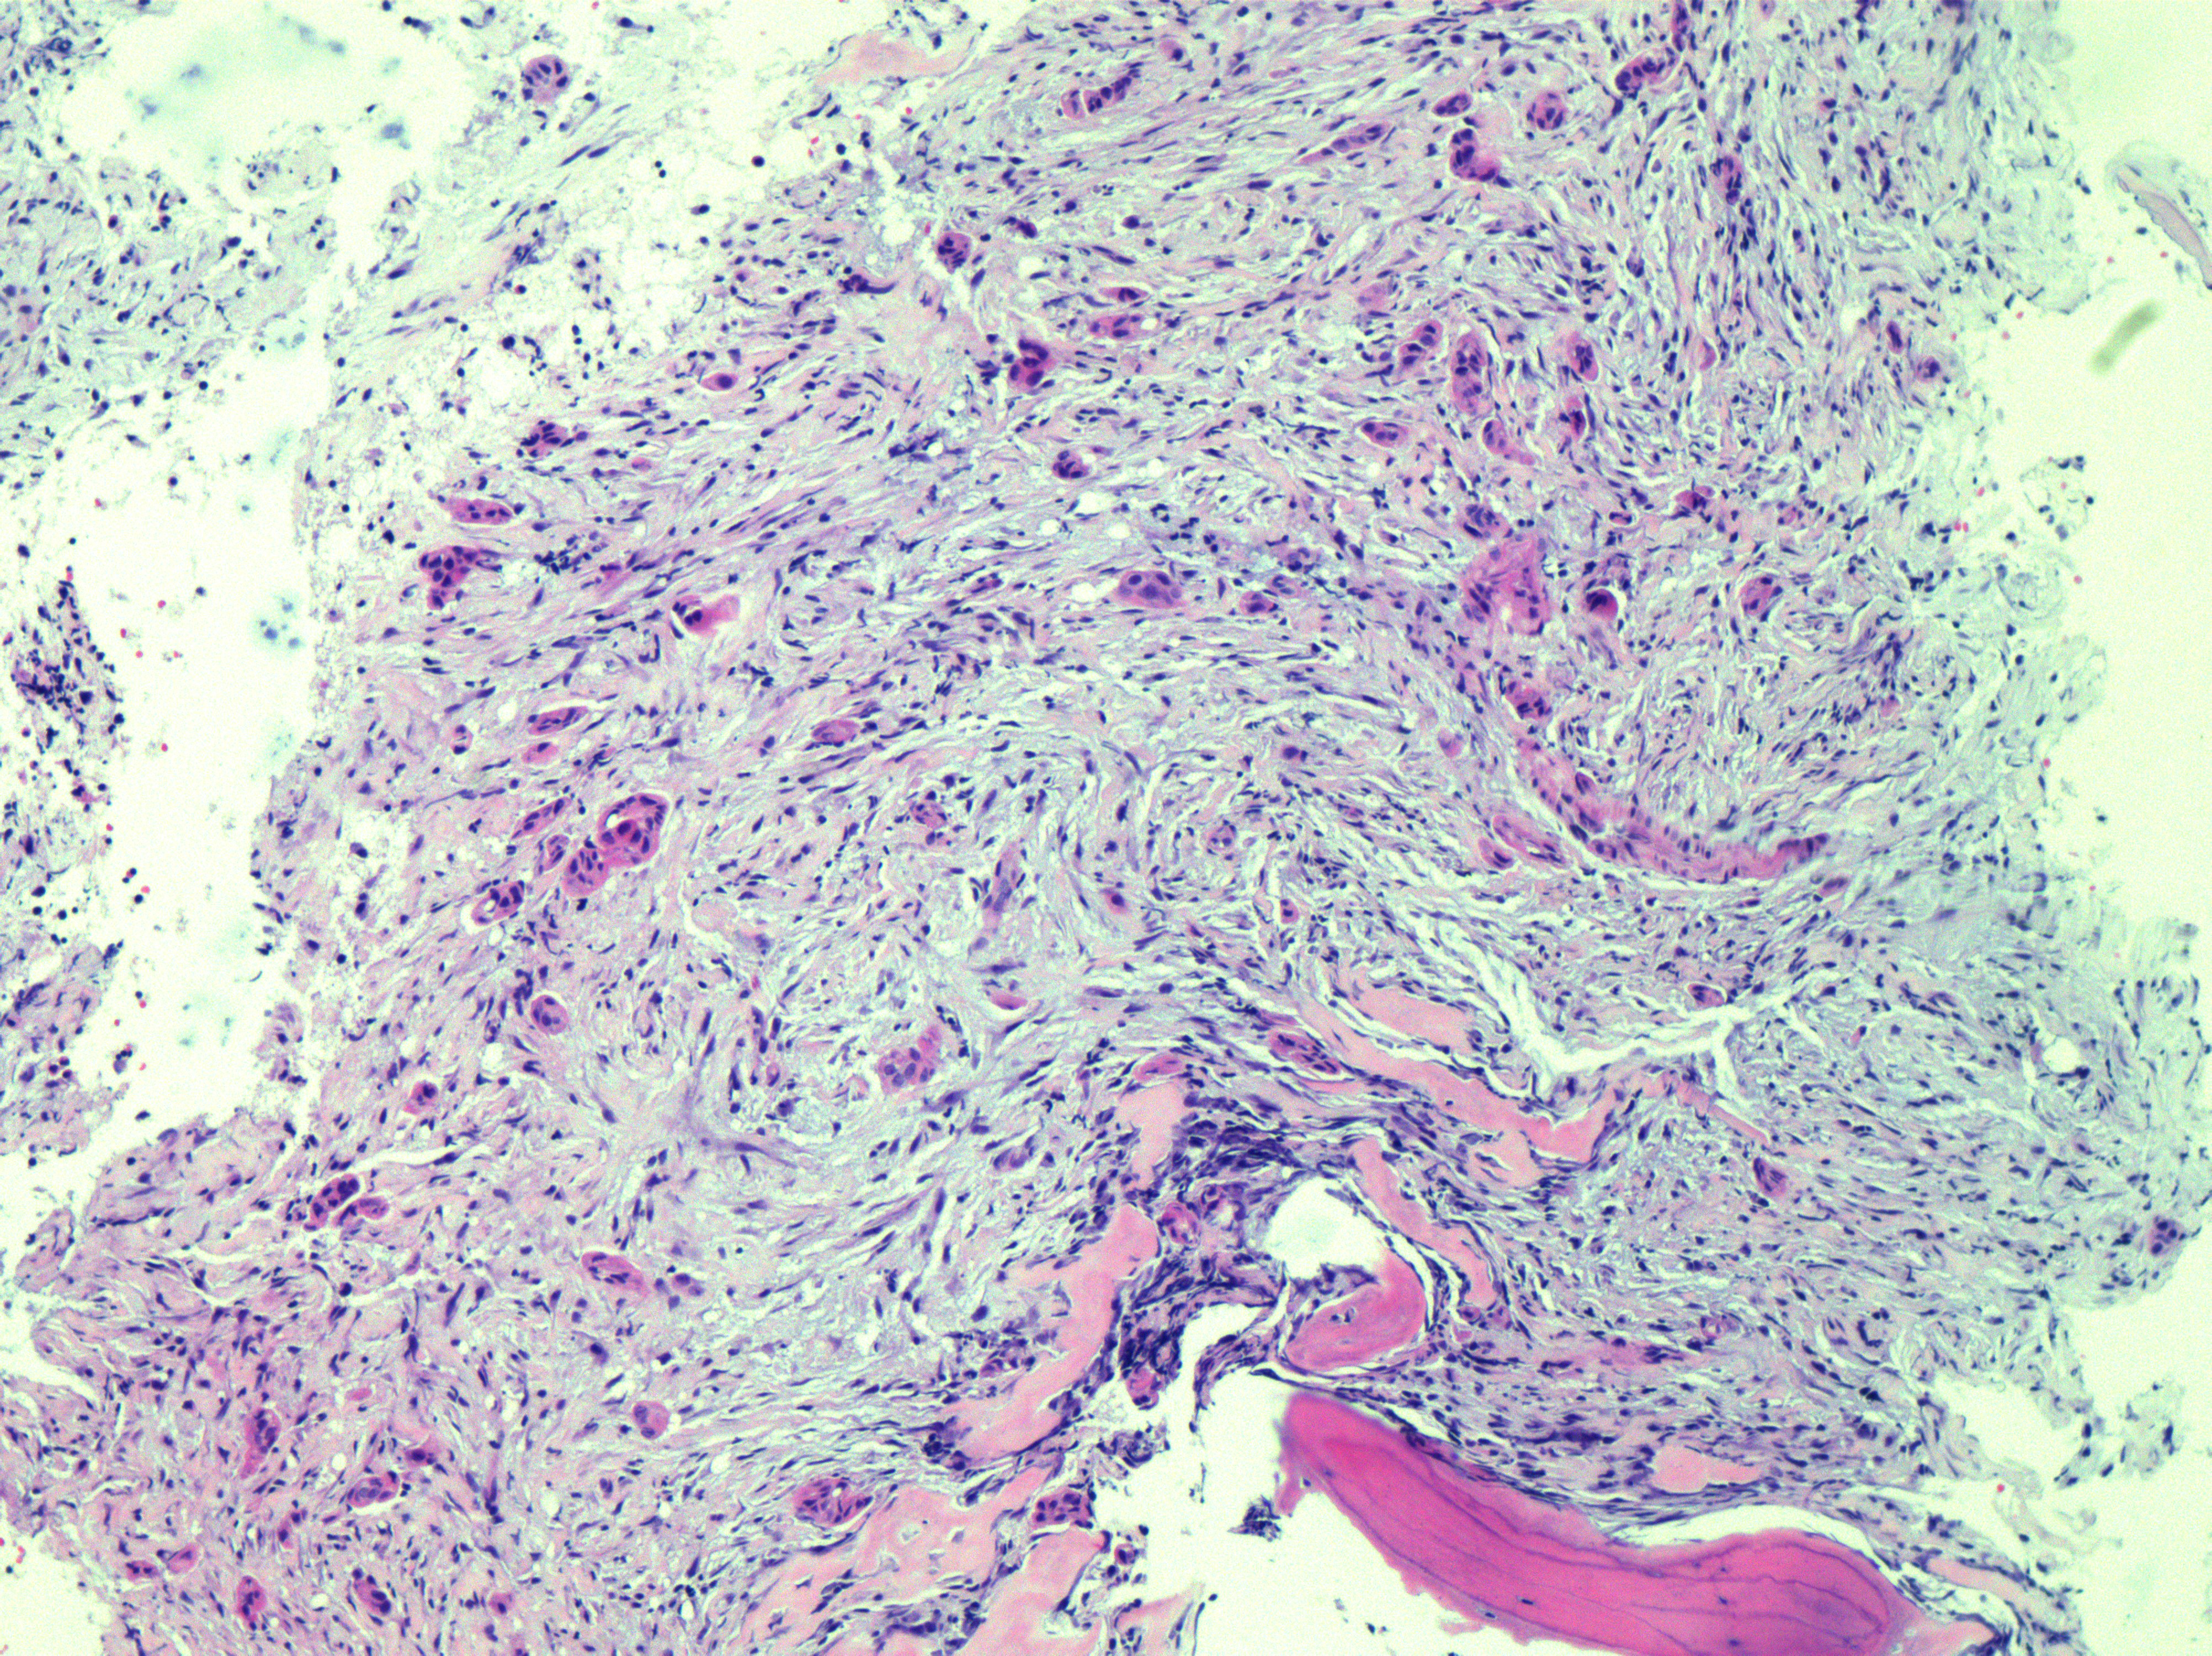

在白先生住院期间,血液科(肿瘤内科)医生王玲对白先生进行了常规骨髓穿刺,并将骨髓标本送到了病理科。病理科医生孔令红在进行显微镜检查时,发现白先生这份标本中存在异常细胞:转移癌。借助病理科的好帮手:免疫组化,力求确定转移癌的原发位置。果然白先生的免疫组化结果出来后,孔令红确定了原发胃癌,立即联系临床科室,为患者进一步诊断。

▲骨髓 HE 10X